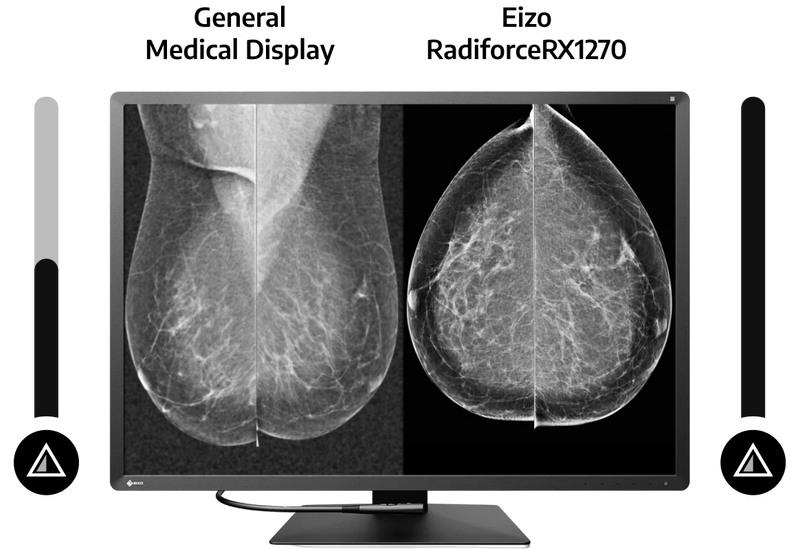

Βέλτιστη οθόνη προβολής μαστού

Το EIZO RADIFORCE RX1270 έχει λάβει την εκκαθάριση FDA 510 (k) από την αμερικανική Υπηρεσία Τροφίμων και Φαρμάκων για την τομοδυνθεσμό του μαστού και τη μαστογραφία. Αυτό εξασφαλίζει ότι το eizo radiforce rx1270 μπορεί να εμφανίσει λεπτομερείς εικόνες προβολής του μαστού όπου είναι απαραίτητη η υψηλή απόδοση.